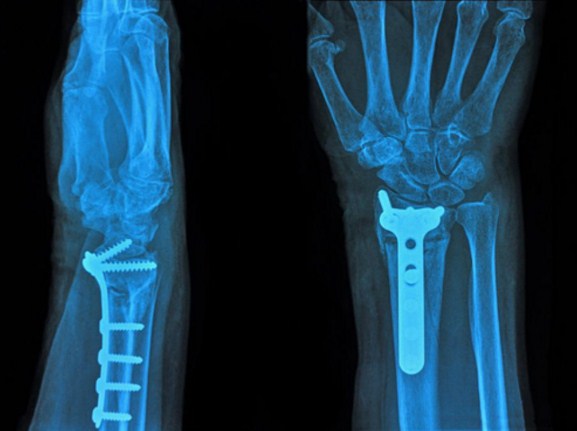

Доклинични изследвания, проведени в болницата в Бомонт, позволяват да се твърди, че подобен биоразлагащ се материал може да бъде използван при лечение на кости на стотици пациенти, нуждаещи се от костна замяна след операции по отстраняване на тумори, спондилоза или тежки счупвания.

Обикновено подобни трансплантации се правят, като се взема кост от друга част на тялото на пациента или от донори. Донорите са малко, вземането на материал от самия пациент често или е неефективно, или просто е невъзможно, затова проблемът с костните транспланти стои доста остро в хирургията.

Кевин Бейкър, директор на Ортопедичните изследователски лаборатории на болницата в Бомонт, казва, че задачата на изследователите е да създадат такъв биоразлагаем материал, който няма нужда от метални или пластмасови вложки за поддържане и усилване на традиционните костни трансплантанти.

„Вътрешното желязо може да стане потенциален източник на инфекции, освен това сериозно може да усложни бъдещи МРТ изследвания. Освен това, от хирургическа гледна точка, когато не трябва да се безпокоим за големи парчета метал или пластмаса в тялото, процедурите протичат много по-леко.“

Биоразлагаемият полимер е подсилен от наночастици монтморилонитна глина и в него е добавен въглероден диоксид, от което материалът прилича на твърда пяна, пореста като истинска кост. Изследователите твърдят, че такъв трансплант се разлага след 18 месеца и за това време организмът вече е отгледал собствена нова кост.